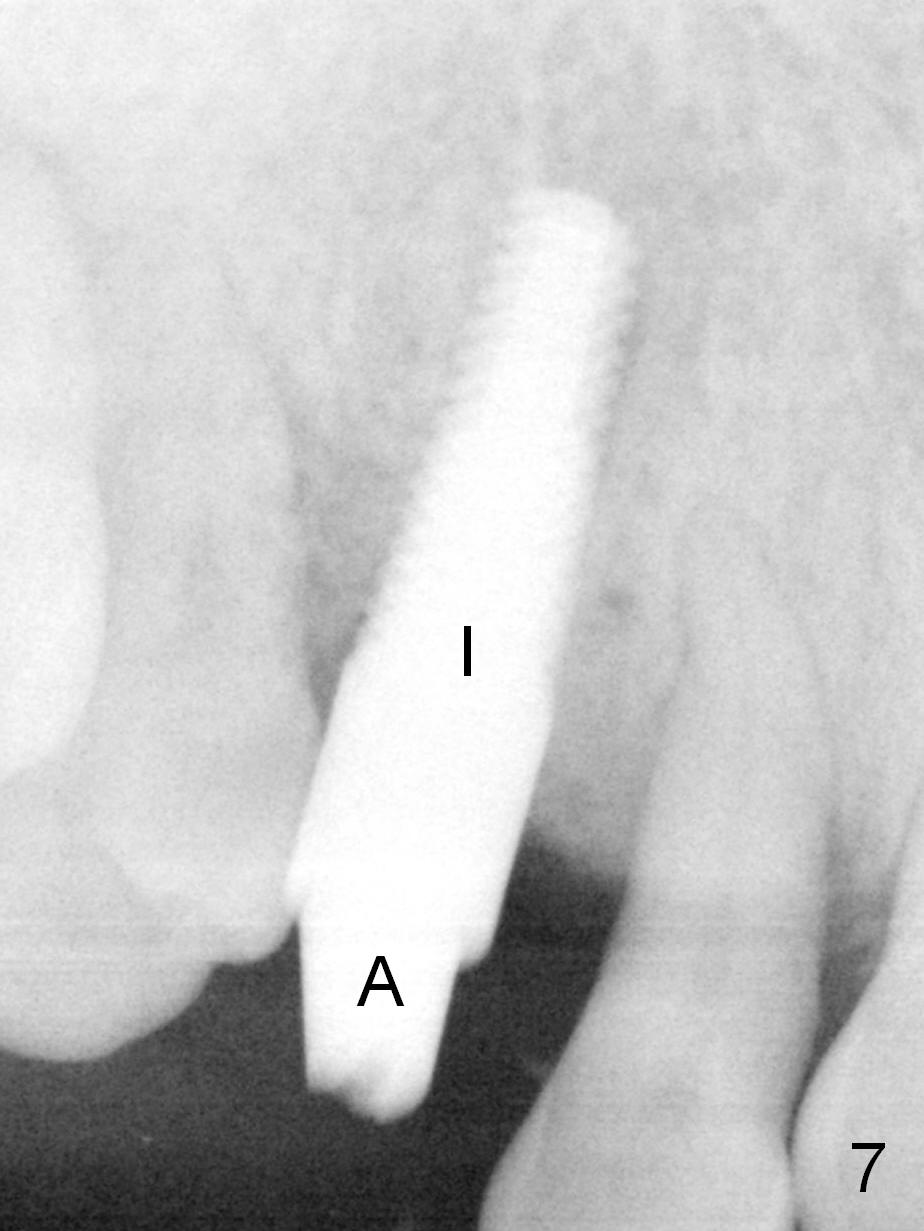

Four months post implant placement, the immediate provisional (Fig.1 P) has mobility with tenderness and perforation at the cervix (^). When the provisional is removed, the buccal plate bulging is more evident (Fig.2 arrowheads). The latter is apparently caused by bone expansion associated with implant placement (Fig.3 black *), since the bulging is not so obvious in a preop CBCT 3 D image (Fig.4 *). There is a layer of fiber granulation tissue (Fig.3 white *) around the mobile implant (I). More fiber tissue is noted when the implant is removed (Fig.5). A new osteotomy is created in the palatal wall of the existing implant site with 2 mm pilot drill, followed by 2.5 and 3 mm reamers. As a 4.5x17 mm tap is being inserted (Fig.6 T), it is deviated buccally. Reamers are re-used to try to remove more palatal bone to let the implant be placed more palatally. When a 4.5x17 mm tissue-level implant is placed (Fig.7,8 I with insertion torque >60 Ncm), there is a small buccal gap (Fig.8 *). A 20° angled abutment (Fig.7,8 A) is placed. An immediate provisional is fabricated with cosmetic satisfaction.